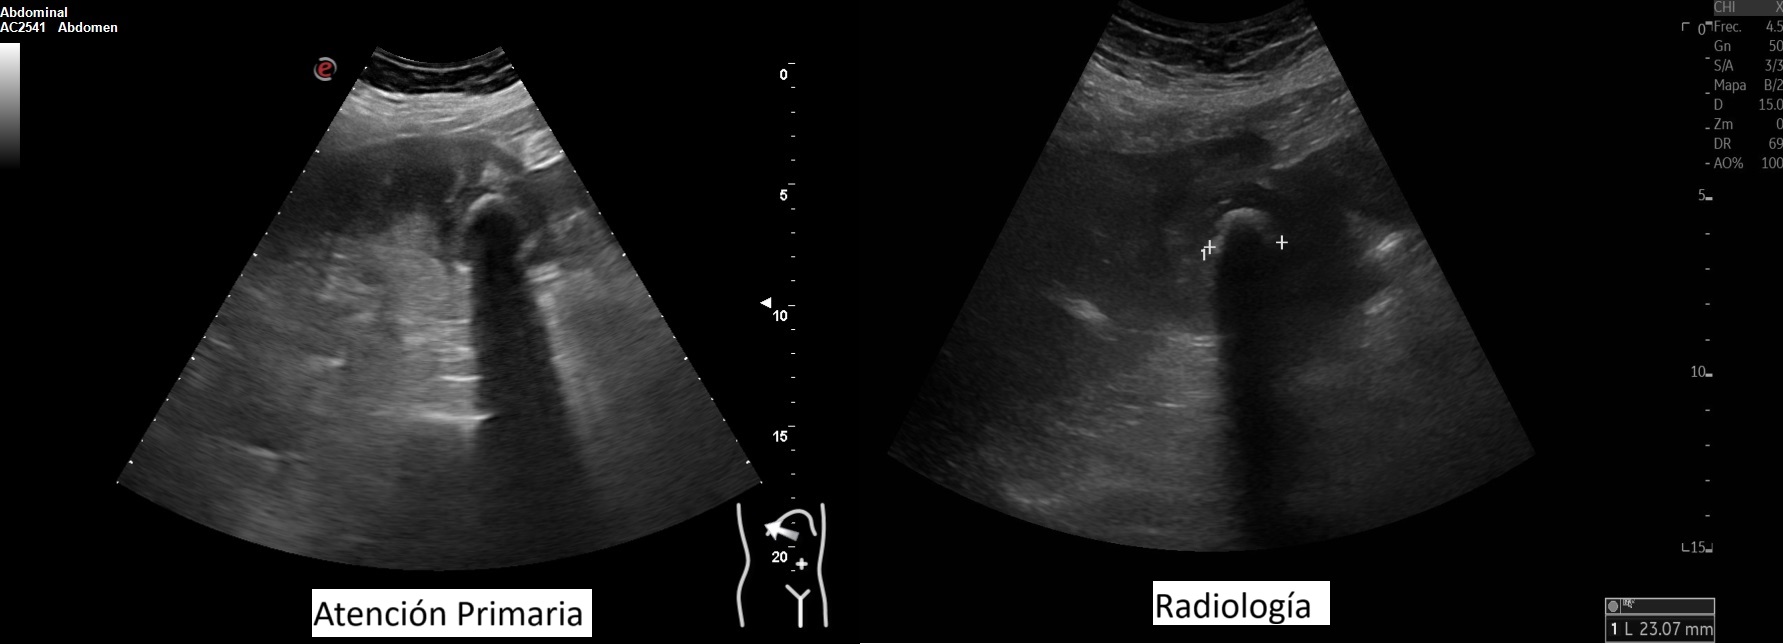

Hallazgos ecográficos

Vesícula biliar desestructurada, de paredes mal definidas con litiasis de 20 mm, que contacta con la pared de la segunda porción duodenal. Porta de tamaño normal. Vía biliar no dilatada.